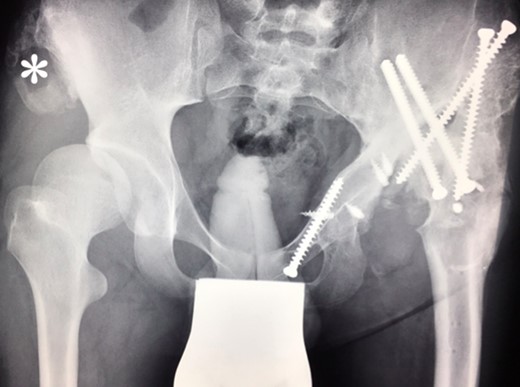

Ten years ago, a 12-year-old male presented to our clinic complaining about limping and massive swelling of the left hip. Figure 1 shows the initial X-ray and the 3D reconstruction of the left hip at first presentation when the femoral head, had already destroyed the lateral edge of the acetabulum like a mortar. Severe pain episodes have apparently not been noticed and a former hip dysplasia was not known. A brief clinical history revealed that the patient presented repeated episodes of finger biting and fevers from 2 to 8 years old. The intelligence level of the patient was at an average. The patient was admitted to a paediatric neurologist and a genetic test. A mutation of the NTRK1 gene was found and the diagnosis of CIPA was established. The right hip initially appeared to be normal and the patient was walking, therefore surgical reconstruction for the left hip was proposed due to massive swelling, inability of normal walking and significant limb length discrepancy. A Tönnis/Kalchschmidt triple pelvic osteotomy with open reduction and a shortening varus derotation osteotomy (VDRO) of the femur was performed (Fig. 2A–B). After 3 months the patient was walking again but another 3 months later the hip dislocated again without severe pain. Although the femoral head was already damaged the hip joint was reconstructed again by open reduction, capsular reconstruction with suture anchors and a trevira tube and a movable external fixator was used to temporary stabilize the joint (Fig. 3). The right hip at this time was still intact and was protected with a pneumatic orthotic device. A few months later in 2009, despite all surgeries, the left hip had entirely lost congruency and the right hip developed subluxation despite conservative treatment (Fig. 4). The patient was still walking so the decision to reconstruct the right hip with open reduction, capsular augmentation with a trevira tube, a triple pelvic osteotomy and VDRO was made (Fig. 5). Few months later this reconstruction failed as well and the hip dislocated without severe pain (Fig. 6).

(2009) Despite conservative treatment the right hip subluxates. There is new bone formation at the proximal os ileum (asterisk) without trauma. The acetabulum is still congruent and decision was made to restore the hip joint by surgery.

At this stage patient’s walking ability was already limited due to muscle weakness and rubbing in the hip joints, so we recommended no further walking and weight bearing. Further follow-up at 5 years (Fig. 7) and 10 years (Fig. 8A) until today showed radiologically complete absorption of the left femoral head and the right hip continuously moving cranially creating a false acetabulum and a flattened femoral head. At final follow up the patient was in a wheel chair but able to bend both hips up to 110 degrees without noticeable pain, he could stand up with help for a short time and showed a massive Charcot joint with effusion (Fig. 8B) of the right hip without further clinical implications.

(2013) Further destruction of any bony congruency at the left side, dislocation on the right side.